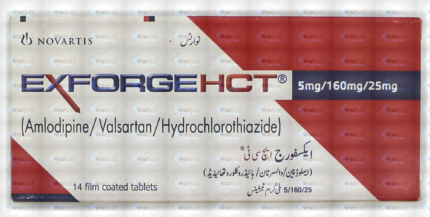

Exforge Hct Tablets 10Mg/320Mg/25Mg (1 Box = 2 Strips) (1 Strip = 7 Tablets)

₹666.00 Original price was: ₹666.00.₹632.70Current price is: ₹632.70.